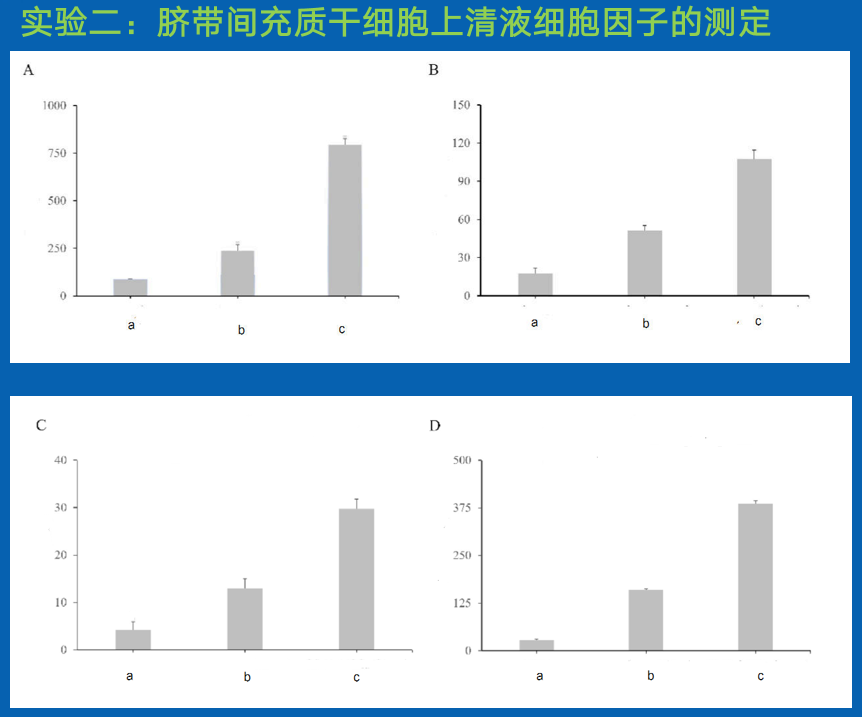

图 3A 为 EGF 含量检测结果(pg/mL),

图 3B 为IGF-1 检测结果(pg/mL),

图 3C 为 KGF-2 含量检测结果(pg/mL),

图 3D为 IL-10 含量检测结果(pg/mL)。

结论:

从测定结果来看,通过添加 KRN 7000 的培养基上清,其中的细胞因子 igf-1、EGF、KGF-2、 IL-10 的表达均大幅度提高。